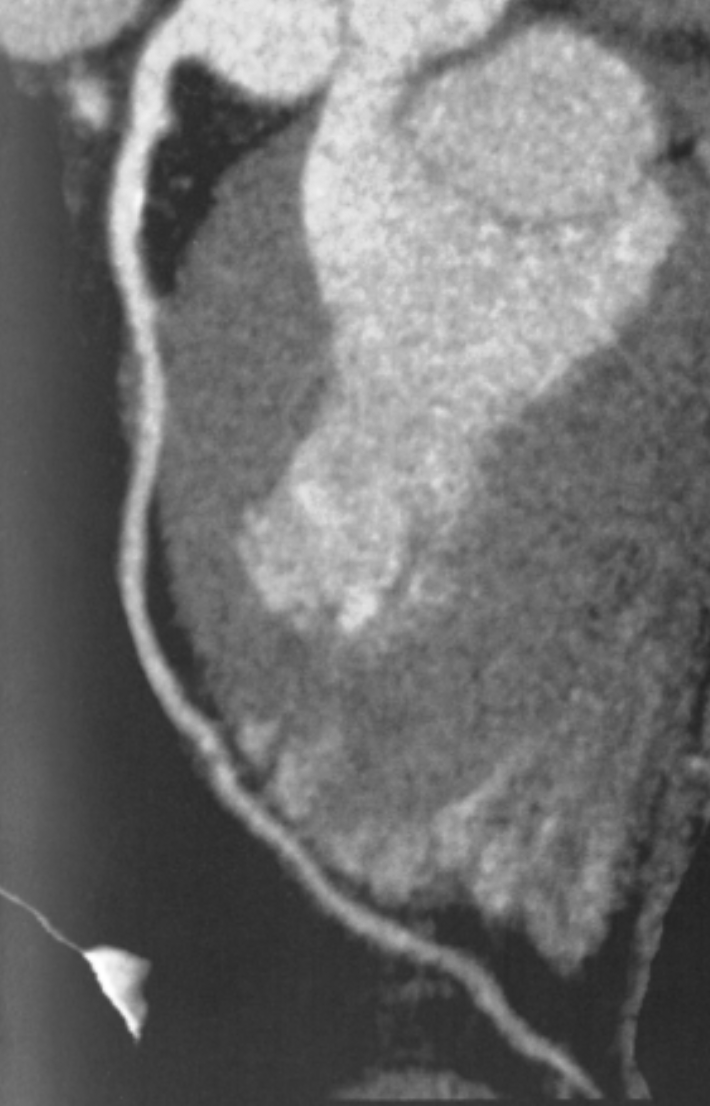

Describe the RCA findings in this image:

Cardiac Motion Artifact